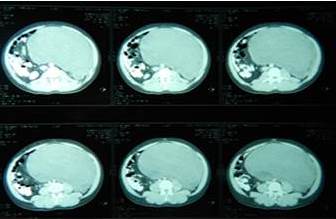

- TAC abdomen y pelvis: gran LOE sólido que ocupa toda la cavidad abdominal desplazando las asas, el colon y el uréter izquierdo hacia la derecha, en íntima relación con la aorta, la cava y los vasos ilíacos izquierdos sin infiltrarlos. Psoas impresiona normal. No hay evidencia de enfermedad metastásica (Figura 2).

La TAC resulta la exploración más importante en la exploración por imagen del retroperitoneo, define mejor que cualquier otra exploración las características de la masa así como la situación de los órganos y estructuras vecinas (cava inferior, riñón, páncreas, psoas, etc.). Puede considerarse como el método más óptimo para el diagnóstico y estadiaje preoperatorio de los tumores retroperitoneales primarios (10,11). Distingue diferentes densidades que sugieren la naturaleza del tumor, define claramente la forma y el tamaño, identifica el atrapamiento o infiltración de los tejidos y órganos circundantes y descubre posibles adenopatías (11). La TAC permite efectuar biopsias guiadas, buscar metástasis y detectar recidivas locorregionales en pacientes ya tratados. En nuestro caso se evidencia la gran tumoración desplazando los órganos abdominales y retroperitoneales, fácilmente se evidencia que no infiltran estos órganos, se pudo evidenciar la relación del tumor con los grandes vasos.